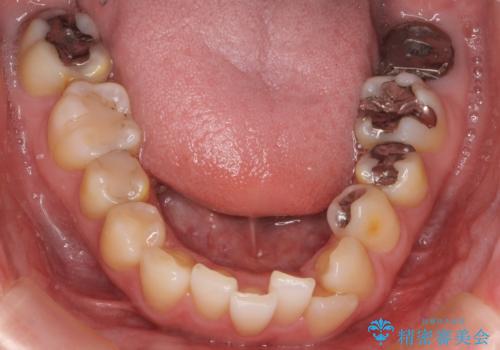

- 前歯の歯並びが気になることを主訴に来院された患者様です。

顎が小さく歯を並べるためのスペースが足りないため、

上下の前歯の歯と歯の間をすく処置(ディスキング)を行いました。

矯正後、右上5左上45セラミッククラウン・右下65左下5セラミックインレーによる補綴治療を行いました。

なお、左下の奥歯(左下7)は状態が悪く保存不可能と判断し矯正前に抜歯しております。